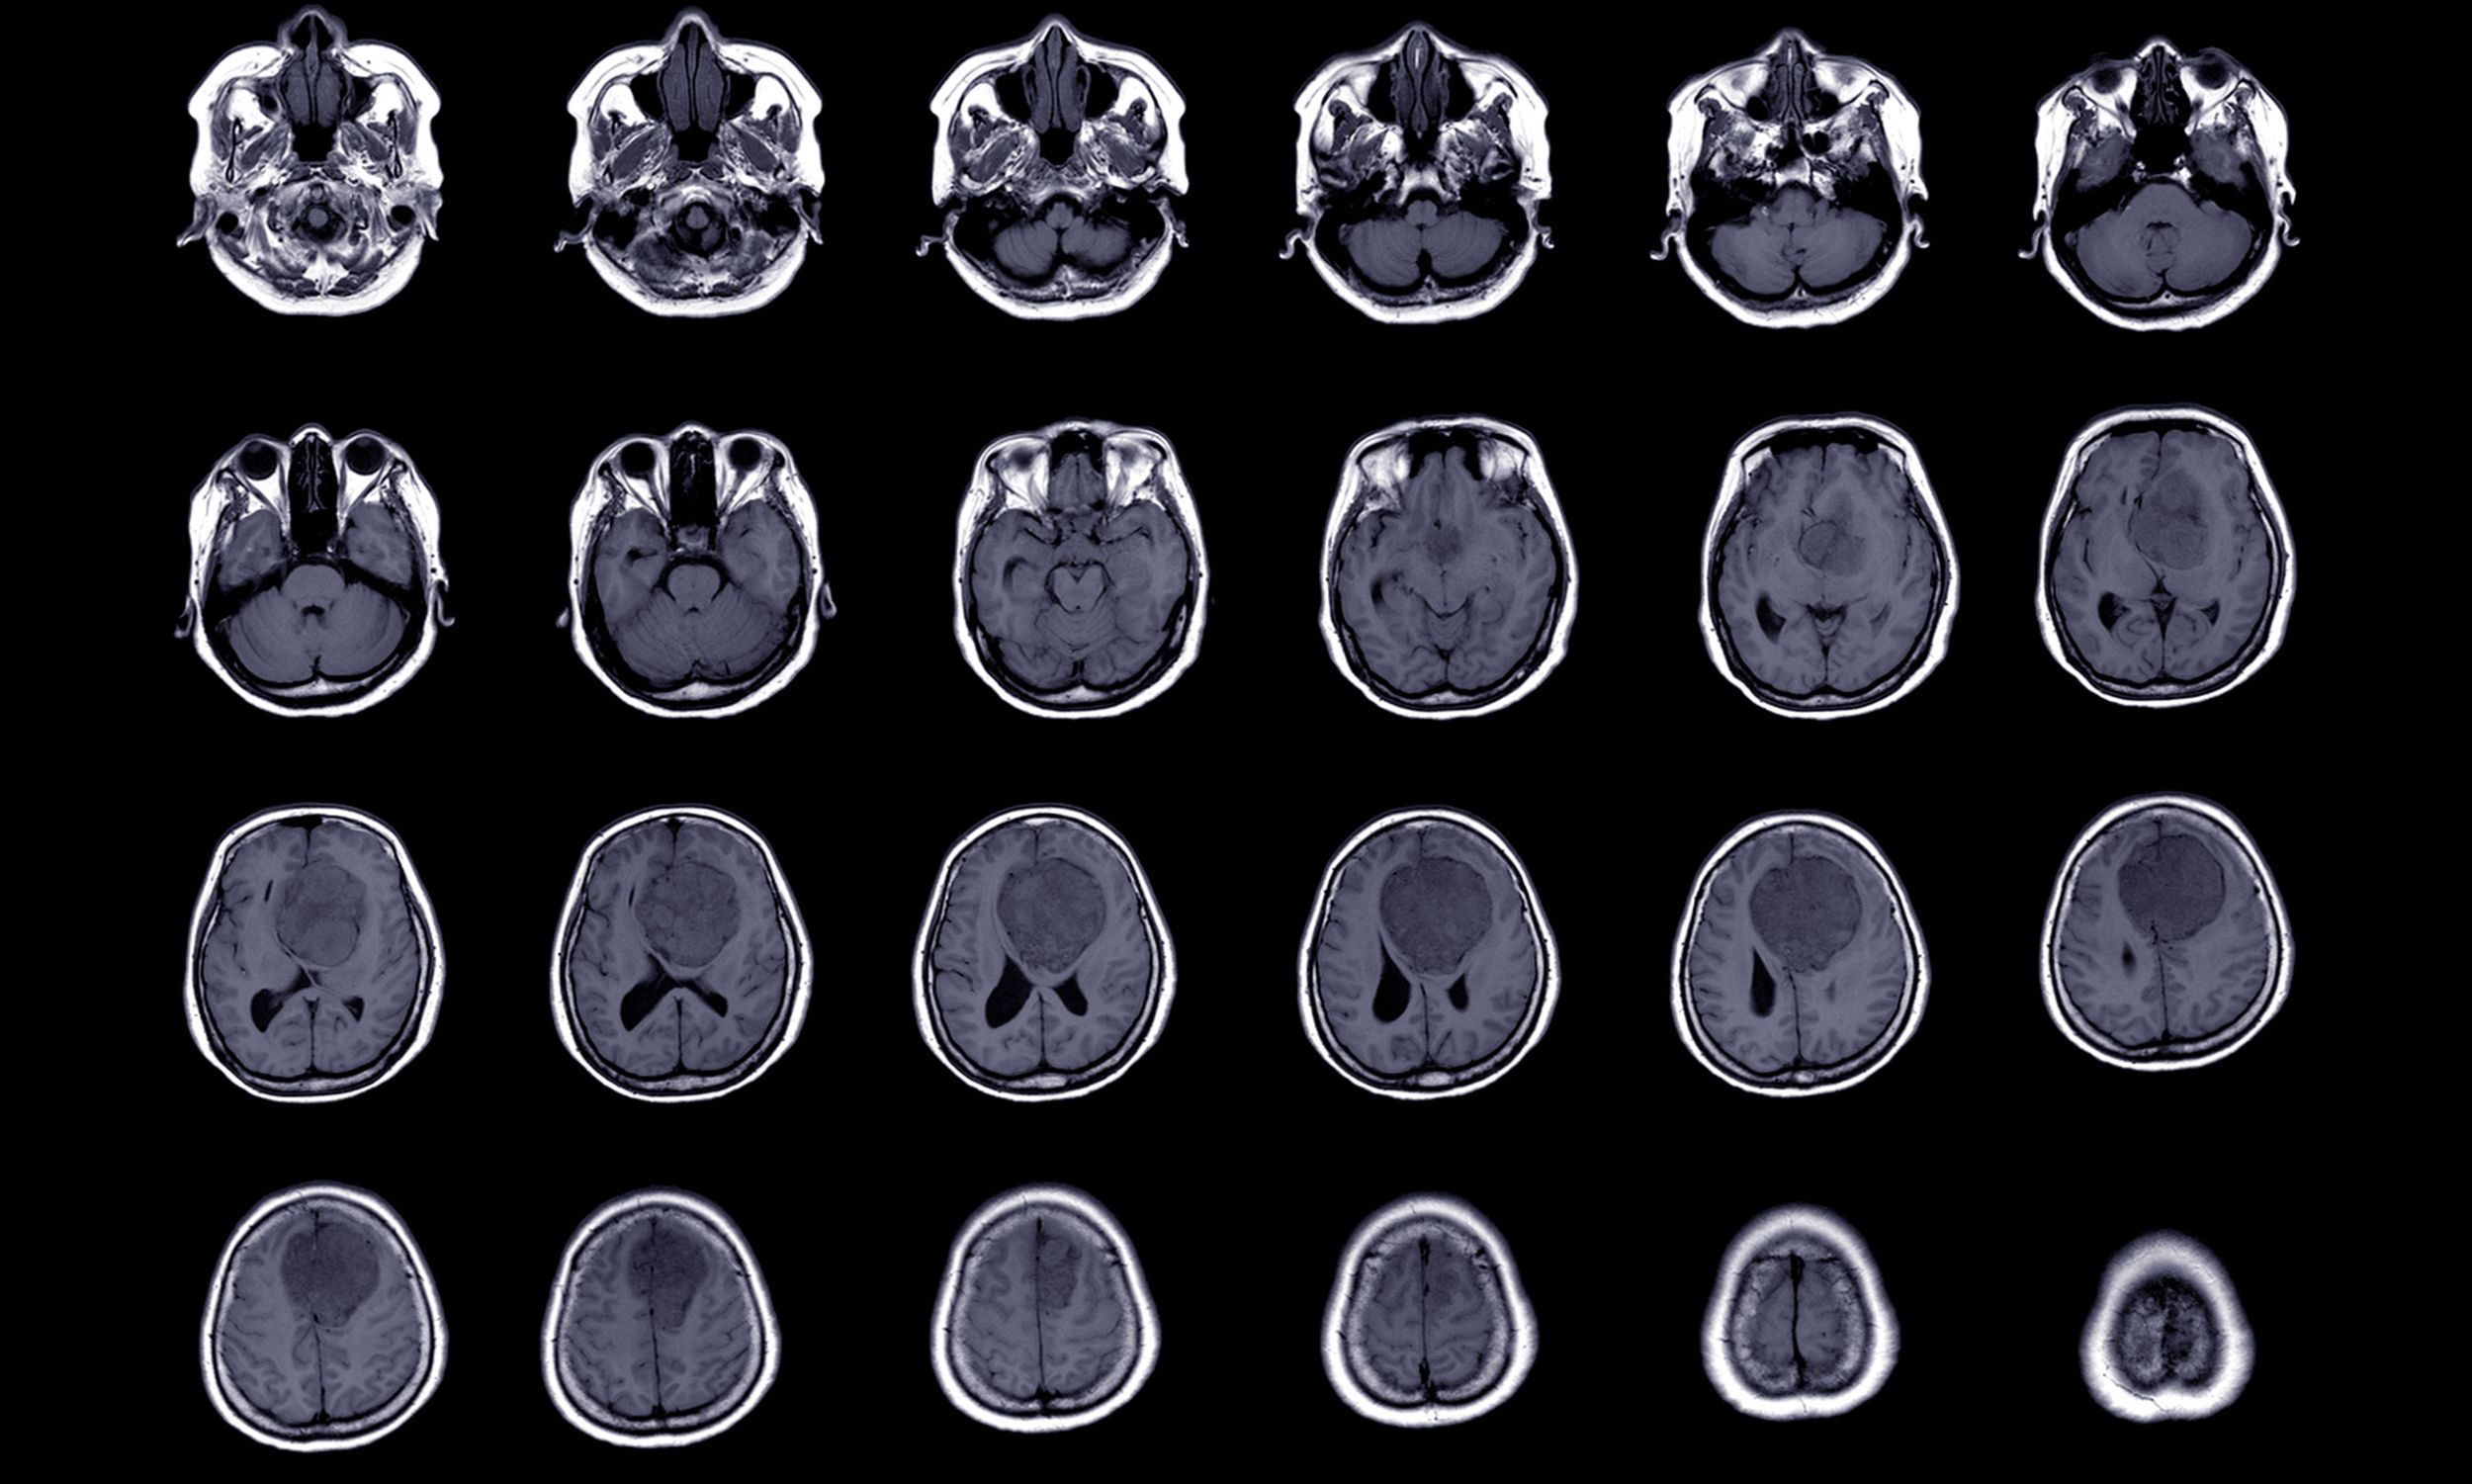

Die Diagnose wird in der Regel durch eine Magnetresonanztomographie (MRT) gestellt. Manchmal wird ergänzend eine Gewebeuntersuchung (Biopsie) durchgeführt, um die Art des Tumors sicher zu bestimmen.